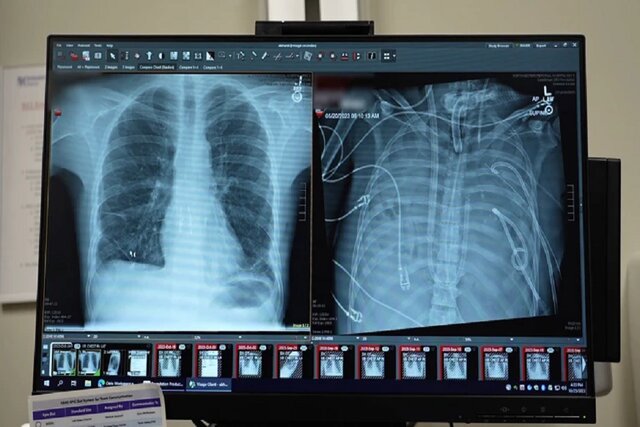

قبل از قرار گرفتن روی سیستم ریه مصنوعی، این مرد دچار سندرم حاد دیسترس تنفسی شده بود که یک وضعیت اغلب تهدیدکننده حیات است که در آن ریهها نمیتوانند اکسیژن کافی جذب کنند و این مشکل توسط ویروس آنفلوانزا ایجاد شده بود. سپس او روی ونتیلاتور قرار گرفت، اما دچار عفونت مقاوم به دارو شد. این عفونت باعث شد قسمتهایی از ریههای او پر از چرک شود و او وارد شوک سپتیک شود که در این مرحله قلب و کلیههایش شروع به از کار افتادن کردند.

بهارات میگوید: او خیلی بیمار بود، دچار ایست قلبی شد و در حال مرگ بود. از آنجا که این مرد خیلی بیمار بود که پیوند ریه دریافت کند، گروه پزشکان تصمیم گرفتند ریههای او را که منبع عفونت بود، بردارند.

به طور شگفتانگیز، مرد شروع به بهبود سریع کرد. در عرض ۴۸ ساعت، او همه داروها برای حمایت از فشار خون را کنار گذاشت، عملکرد کلیه او کاملا بازیابی شد و قلب او به طور طبیعی کار میکرد. در این مرحله، مرد پیوند دو ریه را دریافت کرد و سالها بعد هیچ نشانهای از رد عضو یا اختلال عملکرد ریه نشان نداد. اکنون تقریبا سه سال از انجام این کار گذشته است و حال بیمار واقعا خوب است.